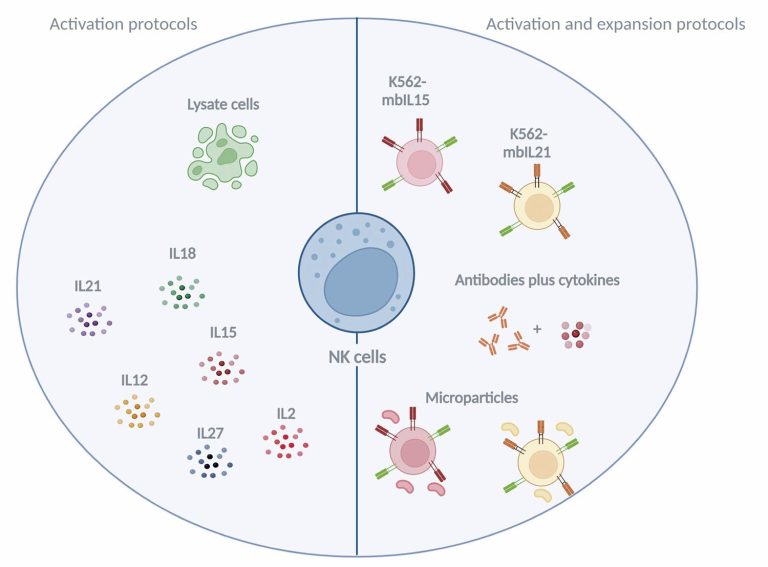

ABSTRACT Natural Killer cells are immune leukocytes required for responses against tumor cells and virus-infected cells. In the last decade, natural killer cells have emerged as promising tools in cancer therapy, and clinical studies on patients treated with natural killer cells have revealed increased rates of disease-free survival. In this article, we review results from the major clinical trials that have used natural killer cells for cancer treatment, including their global distribution. We also discuss the major mechanisms of natural […]